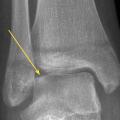

Le diagnostic différentiel est principalement constitué par les fractures. Celles-ci sont spécifiques du fait des particularités de l’os pédiatrique, et le tableau clinique n’est pas toujours aussi flagrant que chez l’adulte. Il n’est pas rare de voir des enfants conserver un appui partiel sur des chevilles fracturées. Dans environ 20 % des traumatismes en inversion, il existe une avulsion de la pointe de la fibula8 (fig. 2), qui doit être recherchée et traitée par une botte en résine durant un mois, quel que soit l’âge. Les décollements épiphysaires de la malléole externe sont beaucoup plus rares que ce qui a longtemps été cru6, et leur pronostic fonctionnel semble bon quel que soit le traitement.